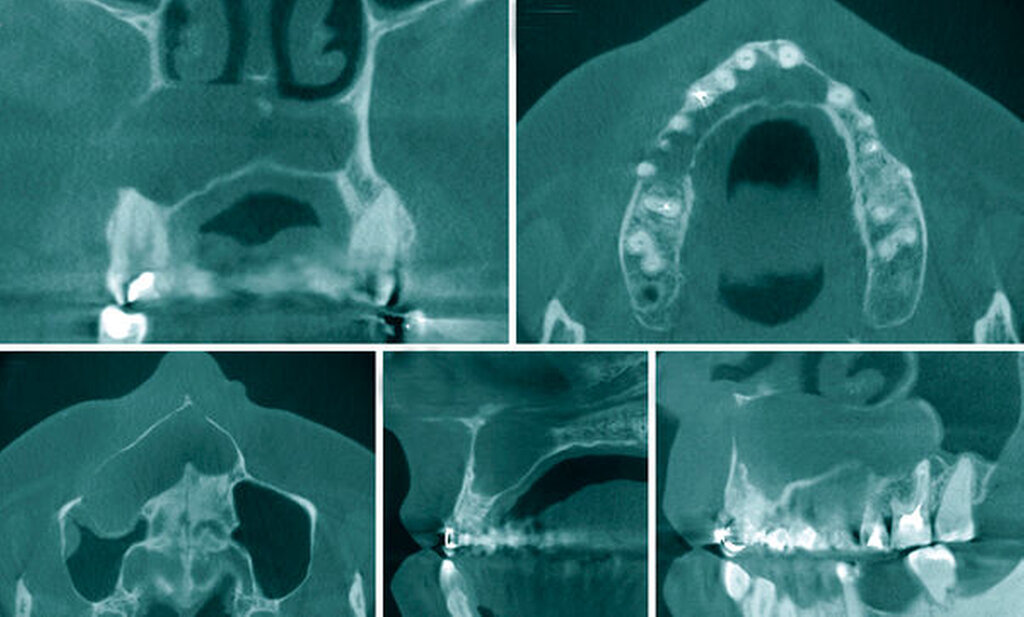

In Intubationsnarkose folgte die Zystektomie (Abbildung 3) über einen marginalen Randschnitt vestibulär regio 17 bis 24.

Dabei wurde die rechte Kieferhöhle über den distalen Zystenanteil im Sinne einer Zystantrostomie eröffnet. Die Zähne 13 und 15 wurden wurzelspitzenreseziert und retrograd wurzelgefüllt sowie die Zähne 14, 12, 11, 21 und 23 orthograd wurzelgefüllt und im Anschluss wurzelspitzenreseziert (Abbildung 4). Intraoperativ wies der Zahn 16 im Bereich der distobukkalen Wurzelspitze eine Paro-Endo-Läsion auf, so dass wir uns entschieden, diesen zu entfernen. Abschließend erfolgten ein Gingivaverschluss sowie die Deckung der iatrogen entstandenen Mund-Antrum-Verbindung in regio 016 mit einem Rehrmann-Lappen.

Die postoperative Wundheilung verlief stadiengerecht, so dass wir die Patientin mit den obligaten Verhaltensmaßnahmen nach Verschluss einer Mund-Antrum-Verbindung am fünften postoperativen Tag in die ambulante Nachsorge entlassen konnten. Das postoperative Orthopantomogramm dokumentiert den Bereich der resezierten Zyste mit seiner Zystantrostomie zur rechten Kieferhöhle, den vollständig entfernten Zahn 16 sowie die durchgeführten endodontischen Maßnahmen (Abbildung 4). Die abschließende Histologie ergab eine radikuläre Zyste ohne Anhalt auf Malignität.